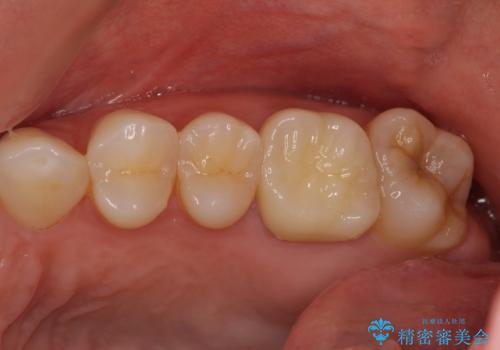

海外転勤が決まり、急いでセラミック治療をしてほしいとご来院された患者様です。

根管治療に症状がなく、上の歯に関しては土台もそのまま使用可能であったため、下の歯の土台、上下の歯のセラミック治療を行いました。

今回は幸い、症状がなく、根管治療の再治療が必要でないため、円滑に治療を進めることができました。